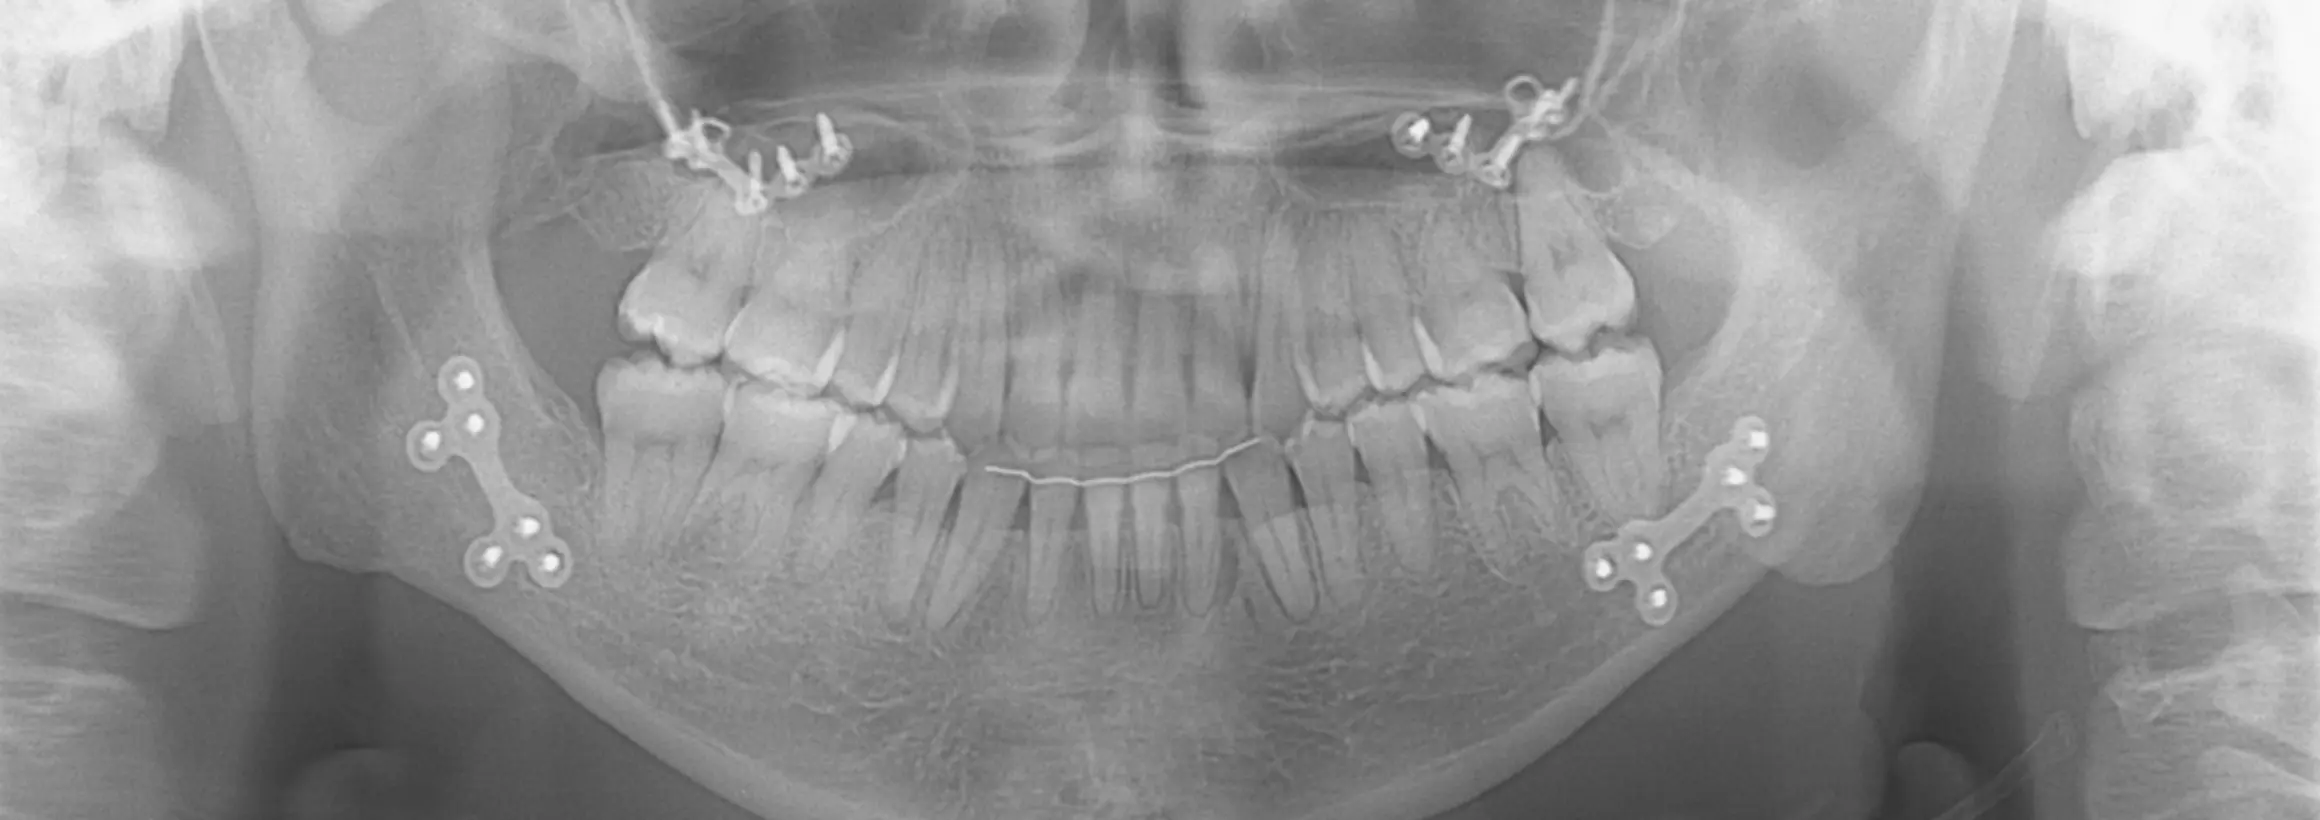

当院では、ほぼすべての種類・形状のプレートおよびスクリューの除去に対応しています。

CT撮影により、現在残っているプレートの位置・種類・本数・周囲組織との関係を精密に評価し、安全性を最優先した除去計画を立てます。